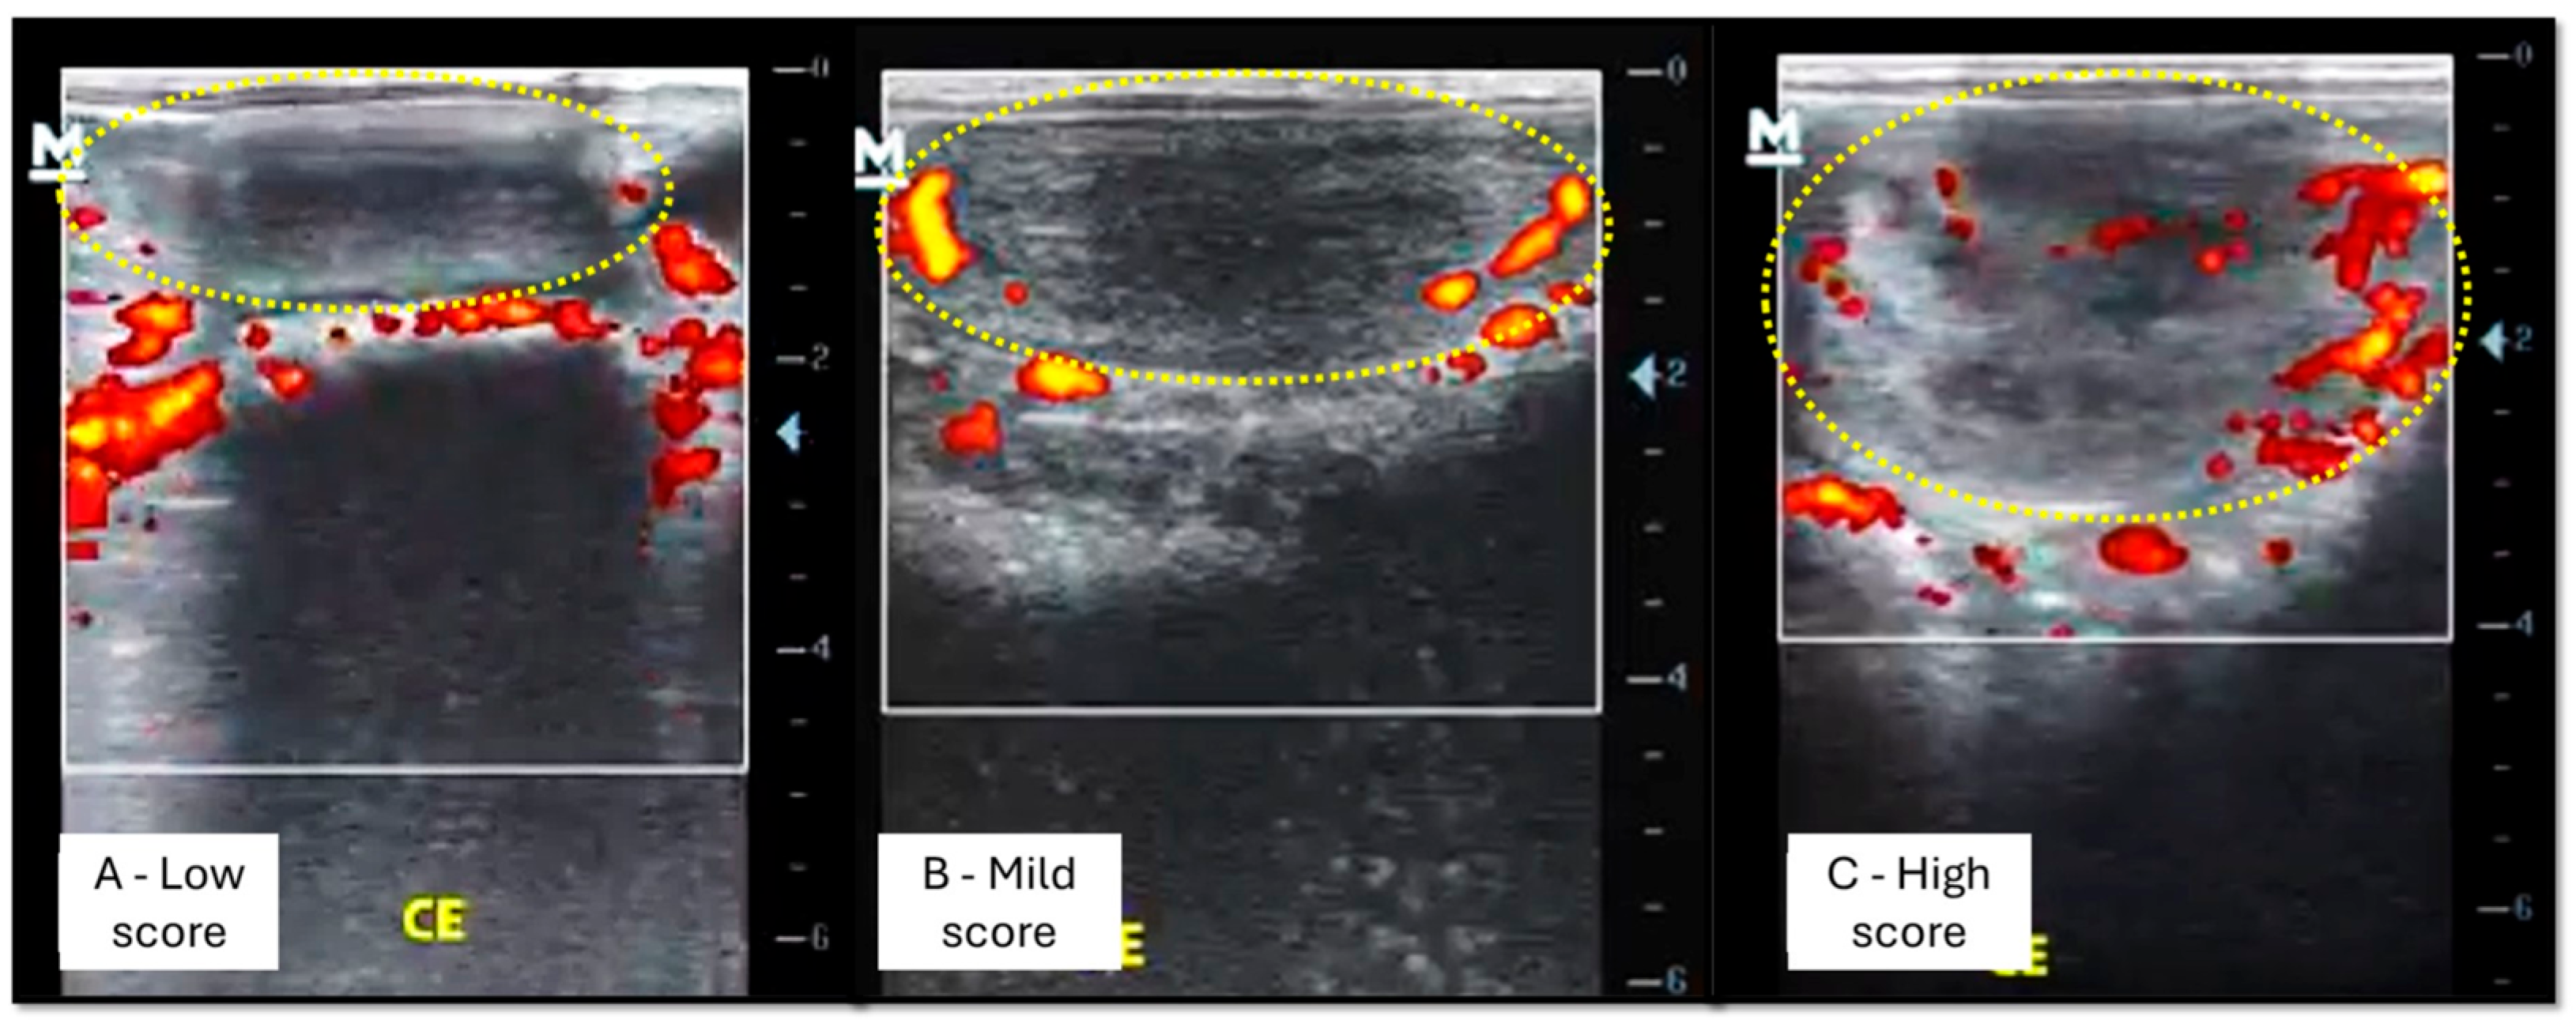

2.4.2. Ultrasound Evaluation